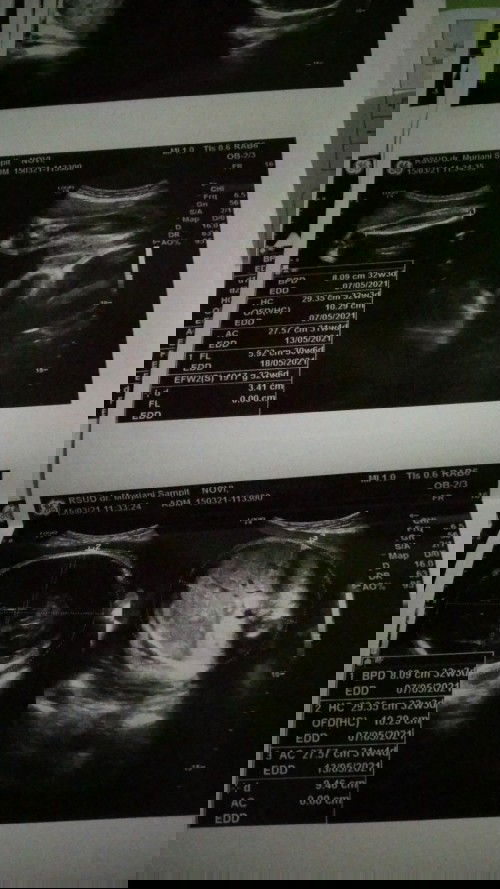

Kehamilan 32 minggu

USG tgl 15 kemaren udah bilang posisi perut bagian bawah sebelah kanan terasa nyeri bahkan bisa sampai di daerah selangkangan kata Bu dokterx ngga apa aja itu Krn posisi debay nya kepala udah di bawah dan aktif ... Pagi ini luar biasa sakitx sampai jalan pun sakit ad ngga yg hpl nya mei tgl 19 merasakan sakit yg seperti ini apa mungkin faktor usia mempengaruhi btw ... Usiaku sekarang 38 th dan ini kehamilan anak ke 6 ku